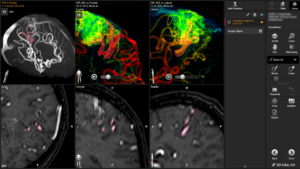

Στην εικόνα 2 φαίνεται μια άλλη χρήση της νευροπλοήγησης, στην περίπτωση αυτή για την αντιμετώπιση αγγειακών δυσπλασιών.